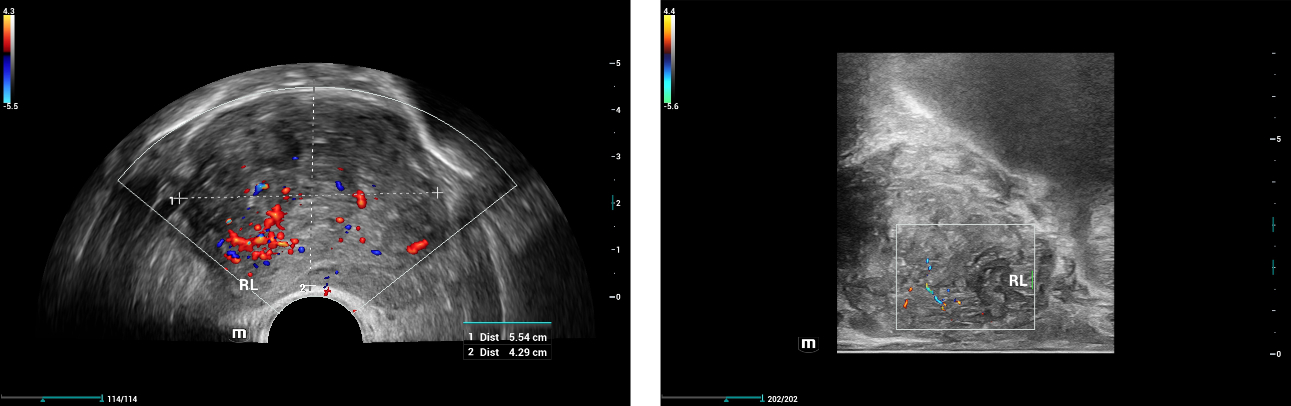

2D color ??? ??:

???? ??? ??? ?? ?? ??? Biplane endocavitary transducer ( ????? Resona i9, ELC13-4)? ??? ??? ??? ?????.

??? ?? ???(SWE)? ??? 34kPa, ??? 115kPa? ?? ??(??6). ?? ??? SWE? ???? ? ???? ? ??.(?? = 19 kPa, ?? = 36 kPa). (??7) ????? ??? ????(PZ)?? ???? ?? ???? ???. ????(TZ)? ??? ???? ?? ????(PZ)?? ? ???. ????(TZ)? ????(PZ)? ??? ???.

6 ?? ?? ??? ?????, 1~3? ??? ???? 4~6? ??? ???? ???????.

2D color ???? RL?? ???? ? ?? ????? ???? ??? ??? ?? ????, ?? ????? ??????? ?? ??? ?? ??? ???? ??? ?? ?? ??? ??? ????? ?????, ???? ????? ???? ???? ??????.